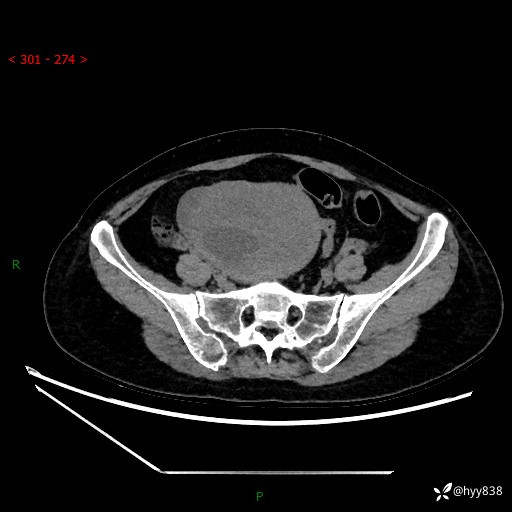

辅助检查:CT

盆腔CT平扫